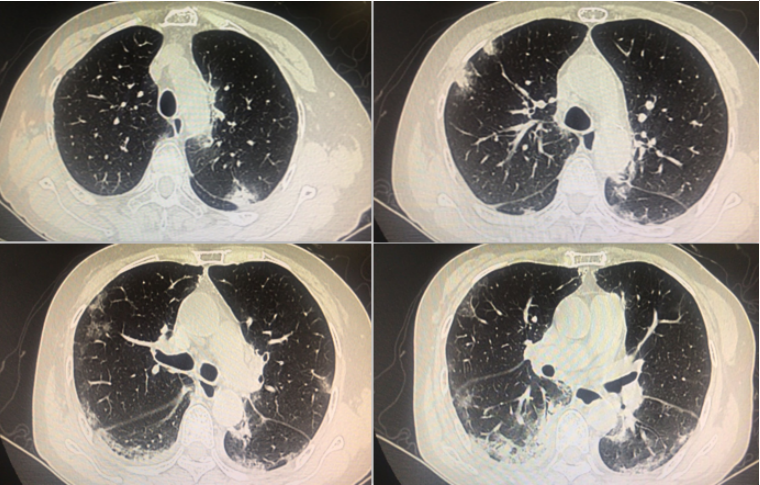

回顾患者病程,2021年3月12日我院PET-CT结果显示肺部已有少许渗出影(图6),至10月患者病情加重,因此考虑皮肌炎可能与胸腺瘤有一定的相关性。

图片

图6  患者PET-CT表现

• 胸部CT(9月27日):两肺间质性肺炎改变(图7)

图7  患者入院胸部CT